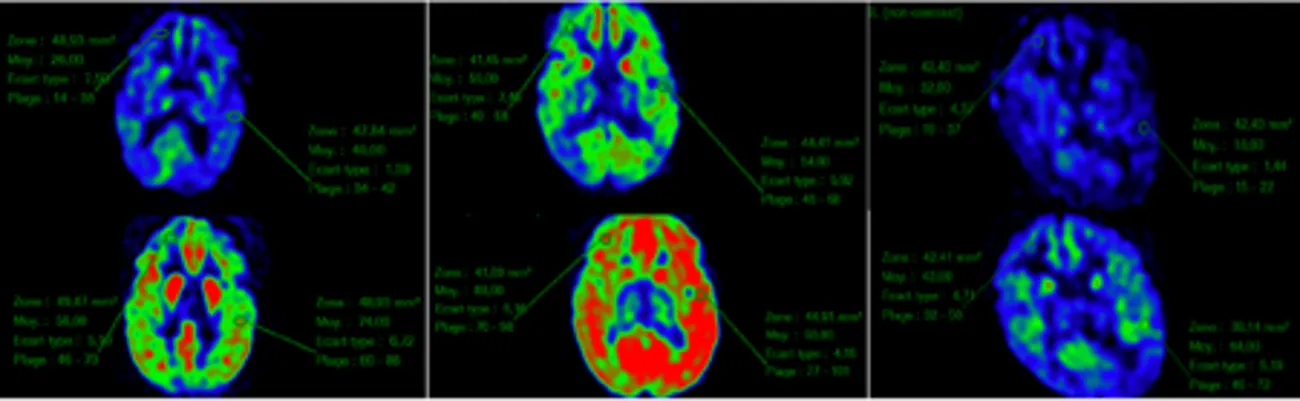

Brain images

The New England Journal of Medicine ©2018.

Since repair of the genetic code in every cell would be impossible, the group decided to treat AGS patients with reverse transcriptase inhibitors (RTIs). RTIs are used to combat the HIV-1 virus that causes AIDS. In the case of AGS it was hypothesised that the same drugs might be able to control endogenous retroviruses driving interferon production. Published in the New England Journal of Medicine, the team of Professor Yanick Crow observed a reduction in interferon levels in affected patients treated over 12 months, with levels of interferon increasing again when treatment was stopped. They also recorded a change in cerebral blood flow during the period of therapy, suggesting that the drugs might be having a functional impact at the level of the brain.